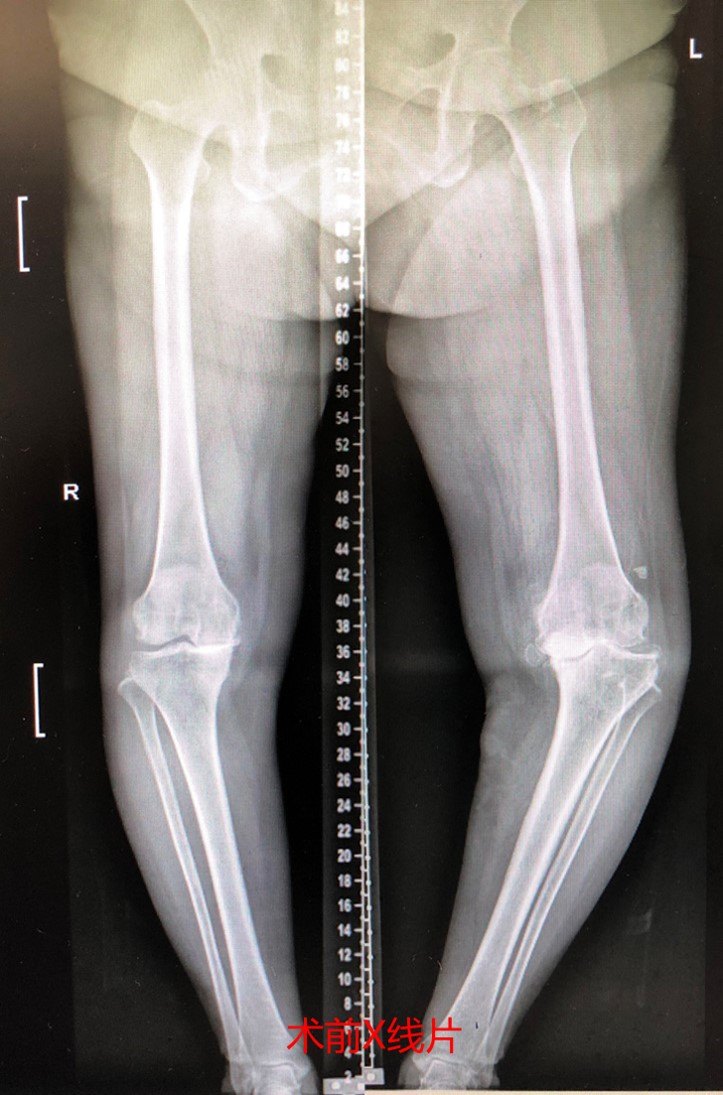

重度膝内翻畸形 完美截骨矫形 内翻38度 - 好大夫在线

a 术前双膝关节正位x线片 b 术前双下肢全长x线片 c 术中缩小胫骨平台

在进行关节手术之前,曲珍患有重度内翻膝,生活已难自理,全靠拐杖支撑